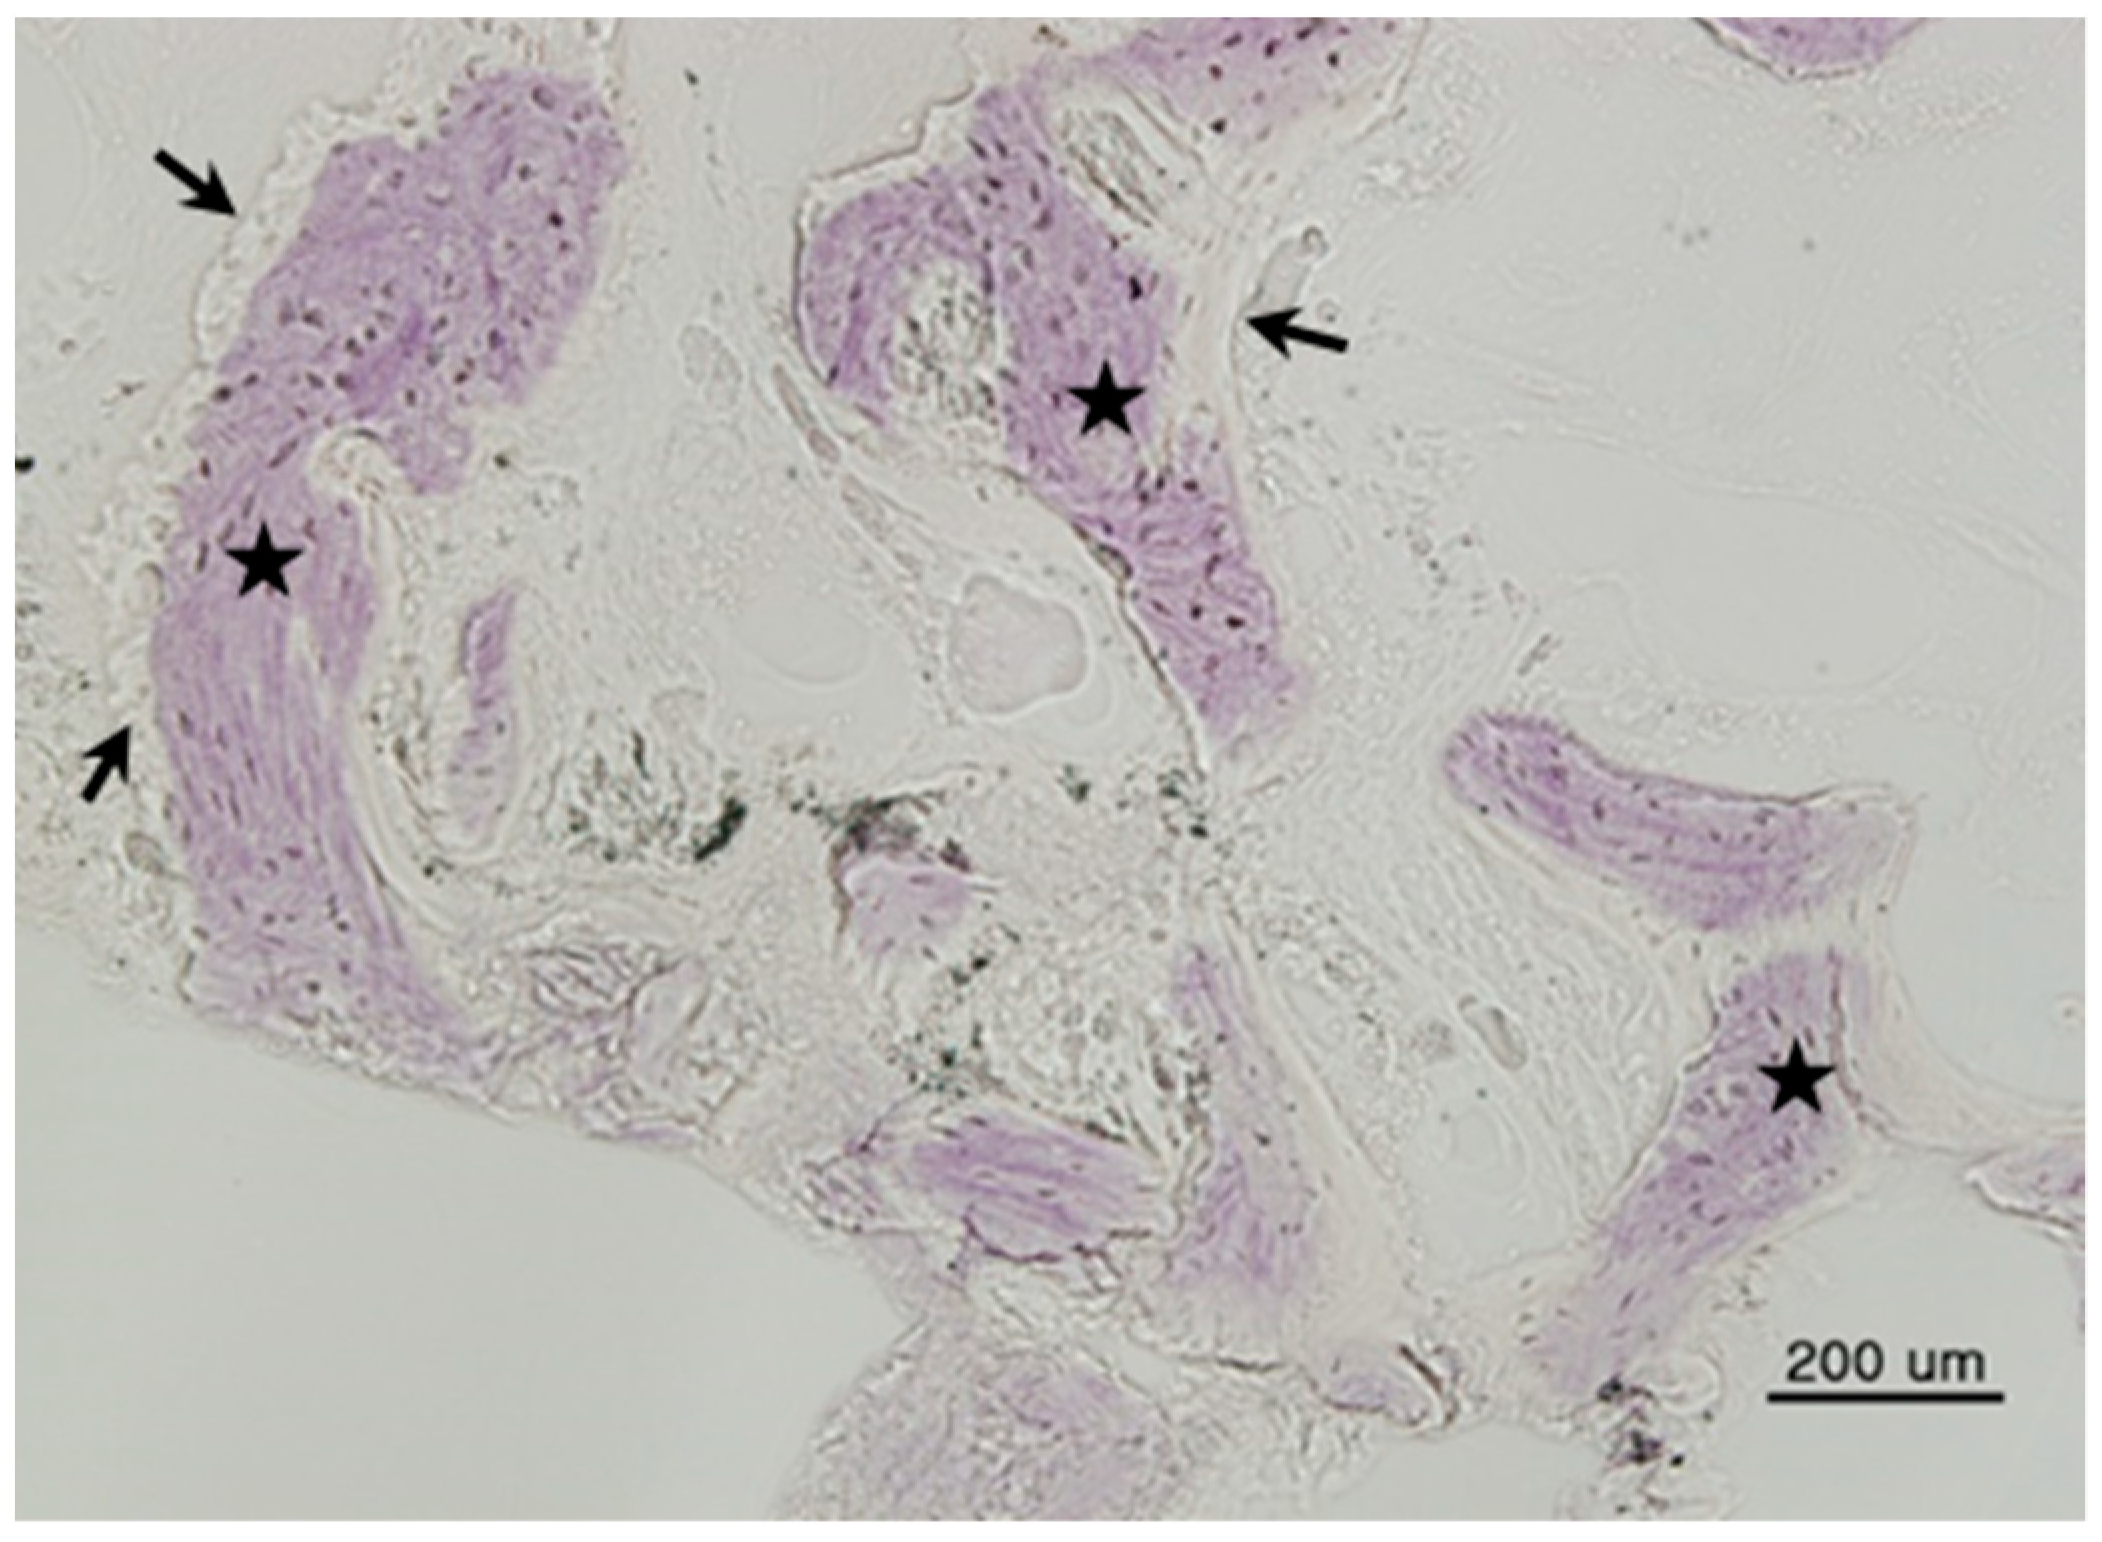

All bone grafts were successfully performed; no inflammation or complications were observed at the surgical site. Mature new bone was found surrounding each implant. Histologic images are shown in Figure 1, Figure 2 and Figure 3.

Figure 1. Histomorphometric image of Group 1 (DBX® + Bio-Oss®). New bone (arrows) was surrounded by bone marrow (asterisks) (hematoxylin and eosin stain, 200×, scale bar = 200 µm).